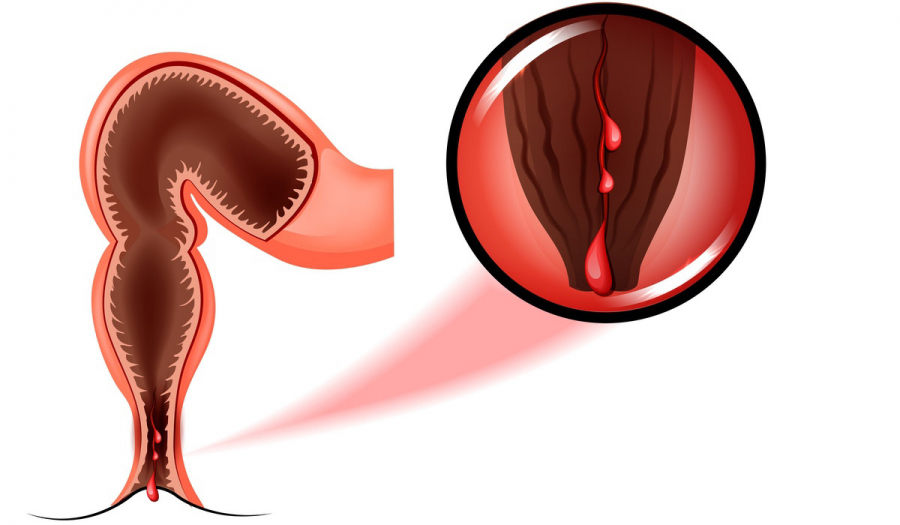

Пацієнти, які скаржаться на біль в задньому проході й виділення крові, часто приписують ці симптоми геморою. Геморой, справді, досить поширене захворювання прямої кишки, однак не єдине з подібними симптомами.